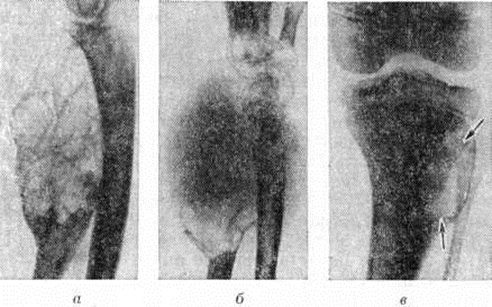

Рис. 1. | ||

Диагноз. В диагностике Остеобластокластома большое значение придают рентгенологическое исследованию. Рентгенологические картина Остеобластокластома в большинстве случаев типичная. Опухоль одиночная, как правило, вначале отличается эксцентричным расположением. Соответственно особенностям роста и локализации Остеобластокластома структура её на рентгенограмме бывает различной. Различают ячеистый и остеолитический варианты строения.

При ячеистом (трабекулярном) варианте наиболее характерным является признак вздутия эпиметафиза с истончением, но сохранением коркового вещества (рисунок 2, а). Поражённая кость приобретает булавовидную форму. Одновременно в результате остеобластической функции опухоли наблюдается грубоячеистая перестройка губчатого вещества эпиметафиза — появление крупных и немногочисленных перегородок, а также более нежной и густой сетки. В этом случае отличить Остеобластокластома от аневризматической костной кисты иногда удаётся лишь гистологически. В структуре опухоли, как правило, отсутствуют отложения солей кальция, контуры Вздутого участка кости достаточно гладки в отличие от энхондромы, которая нередко характеризуется наличием крапчатых теней обызвествления и волнистостью контура поражённого участка кости. Зона поражения чётко отграничена от соседних неизменённых отделов кости тонкой склеротической каймой, образующей вместе с истончённым корковым веществом капсулу опухоли. При распространении опухоли в сторону диафиза можно наблюдать на границе опухоли и трубчатого отдела кости так называемый телескопический переход: диафиз как бы вставлен в нависающий над ним вздутый эпиметафиз. Нередко здесь же определяются полоски окостеневающей надкостницы. Хрупкость коркового вещества, покрывающего опухоль, в некоторых случаях может обусловить возникновение патологический надломов с репаративным, нередко бахромчатым периостозом.

Остеолитический вариант строения Остеобластокластома наблюдается или первично, с самого начала роста опухоли, или вторично, в результате перехода из ячеистого варианта. Рентгенологические картина при этом несколько напоминает остеолитическую саркому. Однако в отличие от неё наблюдается истончение и вздутие коркового вещества, покрывающего изменённый участок кости (рисунок 2, б). Ячеистость структуры полностью или частично отсутствует. Вздутое и истончённое корковое вещество может подвергнуться почти полному рассасыванию, но в основании опухоли, в месте её перехода в неизменённую кость, обычно видны остатки раздвинутого и истончённого коркового вещества, что при остеолитической саркоме, как правило, отсутствует. Так называемый телескопический переход диафиза в опухоль при этом рентгенологическое варианте наблюдается ещё чаще, чем при ячеистом.

Рентгенологически различают центрально расположенные и краевые Остеобластокластома Краевые опухоли (рисунок 2, в) обычно не захватывают центральных отделов эпиметафиза. Диагностика их затруднена, но вполне возможна на основе учёта рентгенологическое признаков — вздутия, ячеистости, отсутствия периостального козырька и другие